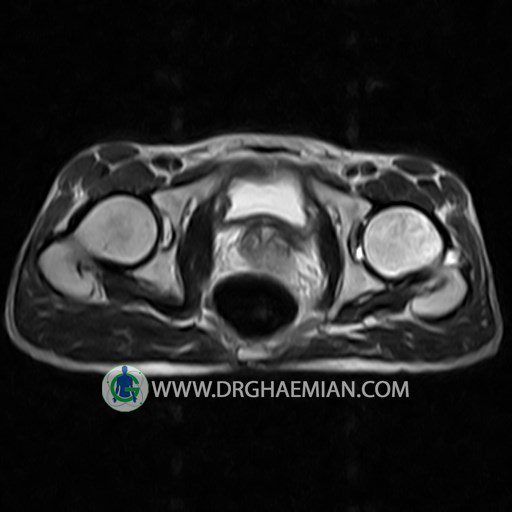

HIP JOINT MRI

( without contrast )

Technique : coronal STIR , coronal T2 , Axial T1 , axial T2 .

REPORT:

The femoral heads and acetabula are normal shape , signal intensity and the femoral heads are well covered by the acetabular margins .

The joint spaces are of normal width without fluid collection .

The articular surfaces are smooth and congruent and show normal cortical thickness .

Each femoral shaft has normal margins and contains a normal bone marrow signal .

The imaged muscles and the lesser pelvis show no abnormalities .

– Heterogeneous signal change (high T2/STIR , low T1) in proximal metaepiphysis of left femur without articular surface irregularity suggestive for bone bruise (stress fracture?), osteomyelitis & arthritis and marrow infiltration (less probable)

– Left hip joint effusion suggestive for synovitis

are seen.

COMMENT: Clinical correlation and MRI with contrast are recommended.